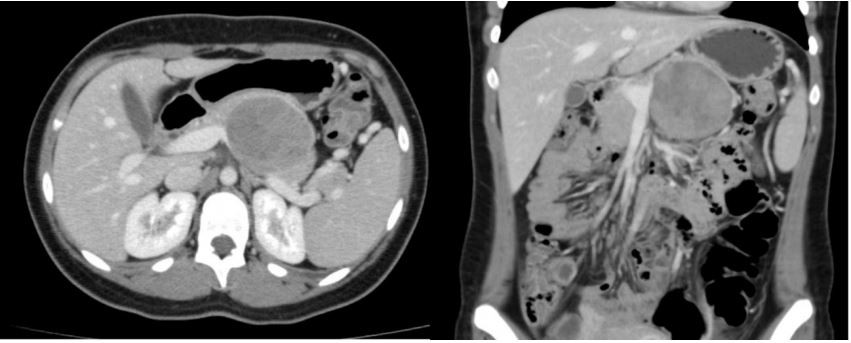

Mulher, 18a, apresenta leve dor em hipocôndrio esquerdo há 4 meses, sem outras queixas. Não possui antecedentes pessoais relevantes. Exame físico: presença de volumosa tumoração palpável em mesogástrio e hipocôndrio esquerdo. Realizada tomografia computadorizada de abdome superior, apresentada abaixo:

Considerando a topografia pancreática da lesão, assinale a alternativa que contenha a hipótese diagnóstica mais provável e o tratamento indicado: